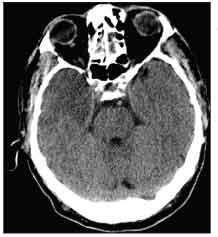

Figure 1 –This CT scan of the head shows a hypodense lesion of the right anterior temporal lobe.

Lorazepam (2 mg), vancomycin (2 g), ceftriaxone (2 g), and ampicillin (2 g) were administered intravenously. A CT scan of the patient’s head revealed a hypodense lesion of the right anterior temporal lobe (Figure 1). A cerebrospinal fluid (CSF) sample was clear, with a WBC count of 7/µL (4% neutrophils, 89% lymphocytes, and 7% monocytes), a red blood cell count of 15/µL, a serum glucose level of 84 mg/dL, and a serum protein level of 66 mg/dL. Gram stain results were negative. An electroencephalogram (EEG) showed periodic lateralized epileptiform discharges (PLEDs) at 2-second intervals in the right anterior temporal region with generalization.